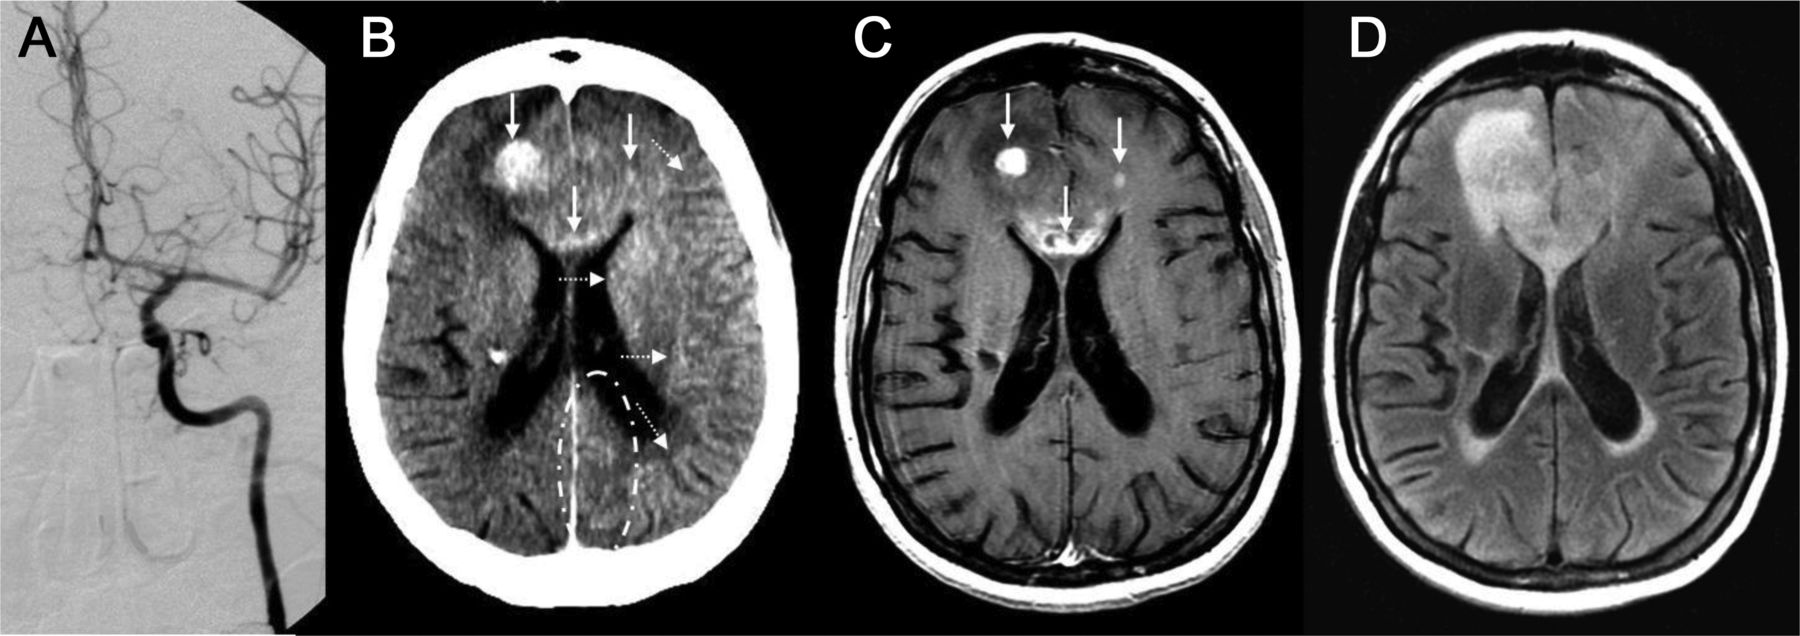

立即后动脉内的溶栓头CT (A)展示了一个新领域内的hyperdensity离开豆状核(A)。十四个小时postprocedure头部CT显示持久hyperdensity,损失的灰白色分化在左parieto-temporal凸性,并抹杀左侧侧脑室CT扫描主管(b)。随访36小时,60个小时持续hyperdensity左壳,建议外渗与脑水肿和中线移位(c, d)。头部CT动脉内的溶栓后立即(b)显示了一个hyperdensity正确的硬膜(A),解决完全重复头上CT表现16小时postprocedure (b),显示对比度增强。

几个机制假设对比造影剂外渗和出血有关。19最有说服力的毒性在基板,包括对比BBB的结构性障碍与干扰。它导致溢出的血液细胞元素从微血管,反过来,导致对比外渗(定义为hyperdensity暗示对比[Hounsfield单位> 90])在24小时(图4A)。相比之下,对比度增强是由于从血管造影剂泄漏到细胞外空间,由于BBB的渗透性增加。头部CT二次的hyperdensity对比度增强通常在24小时内清理(图4B)。对比溢出已被证明有一个强大的协会与HT以及预后不良。20.